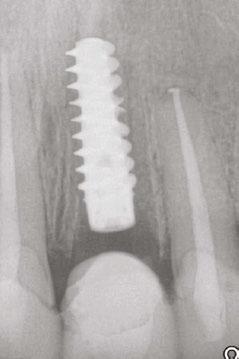

An 80-year-old male with a relatively clean medical history was referred for full-arch immediately loaded maxillary implant treatment. The patient had been previously treated with maxillary dental implants in a traditional All-on-X approach. The referring clinician noted that the patient’s bone was extremely “soft” and that insertion torque for most of the implants was very low. Although these implants were not immediately loaded, they ultimately failed and created large oroantral communications. While the communications were ultimately closed, extremely large

Figure 5 (left): CBCT slice (axial view) to determine Simmen classification.

Figure 6 (right): CBCT slice (axial view) for mediolateral measurement of prelacrimal bone width

Figure 7 (left): CBCT slice (sagittal view) for vertical measurement from subnasal bone to prelacrimal bone engagement point. Figure 8 (middle): Panoramic radiograph of patient with history of failed All-on-X treatment, oroantral fistulae, and thickened Schneiderian membranes. Figure 9 (right): Intrasurgical photo of transnasal dental implant traversing the nasal cavity and engaging the base of the inferior concha

defects resulted in the floor and walls of the maxillary sinuses (Figure 8). CBCT analysis revealed a significantly thickened left Schneiderian membrane and occluded osteomeatal complex. The patient was referred to ENT for a Functional Endoscopic Sinus Surgery (FESS) procedure. Upon healing, a new CBCT was taken and evaluated for potential treatment.

Due to the atrophic nature of the maxilla, treatment following the PATZi protocol was planned.6,17,20 CBCT evaluation revealed pterygomaxillary bone appropriate for pterygoid implants allowing for posterior arch support and cantilever elimination. The zygomas were of adequate height and width to accommodate multiple zygomatic implant fixtures bilaterally. PLACATE guidelines were used to evaluate the patient for potential treatment with transnasal implants. With Simmen 3 nasolacrimal canal classification, ≥ 3 mm of prelacrimal bone, ≥2 mm subnasal bone, and ≤ 25 mm to the Z-point, the patient satisfied all PLACATE parameters. Accordingly, a treatment plan of bilateral pterygoid, single zygomatic, and transnasal implants was agreed upon.

Following the induction of general anesthesia, extraoral and intraoral local anesthesia was applied. To avoid exposing the large subantral bony defects, mini-flaps were elevated at the pterygoid landing areas to expose the hamular notch. The pterygoid fossa was identified via probing, and pterygoid implant placement ensued. Following the PATZi protocol, bilateral pterygoid implants were placed first and both achieved insertion torque between 45+ Ncm.

Following PATZi, anterior support was sought next. As such, the nasal mucosa was elevated to expose the floor of the nasal cavity and the bone of the inferior conchae. A pair of 25 mm transnasal implants were placed, and each achieved high insertion torque of 45+ Ncm (Figures 9-11). Continuing with the PATZi protocol and treatment plan, 42.5 mm long zygomatic implants were placed in both zygomas. The zygomatic implants were placed using an extrasinus approach and both achieved insertion torque of 45+Ncm. Buccal fat pedicles were advanced bilaterally to cover extrasinus portions of the zygomatic implants, and flap closure was achieved with 4-0 chromic gut suture. The patient was immediately temporized with a screw-retained transitional bridge (Figure 12), and a final zirconia restoration was delivered after 8 months of healing (Figure 13).

Figure 10 (left): CBCT slice (coronal view) of transnasal dental implants engaging the Z-point. Figure 11 (middle): CBCT slice (sagittal view) of transnasal dental implant engaging prelacrimal bone ventral to the nasolacrimal duct. Figure 12 (right): 3-dimensional CBCT rendering of patient treated with transnasal, zygomatic, and pterygoid dental implants via the PATZi protocol

Figure 13: Panoramic radiograph of patient with final zirconia restoration